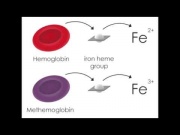

| 07:38, 3 ביולי 2017 | מטהמוגלובין3.jpg (קובץ) |  |

16 קילו־בייטים | Motyk | 1 | |

| 07:34, 3 ביולי 2017 | מטהמוגלובין2.jpg (קובץ) |  |

16 קילו־בייטים | Motyk | 1 | |

| 07:30, 3 ביולי 2017 | מטהמוגלובין1.png (קובץ) | 41 קילו־בייטים | Motyk | 1 | ||